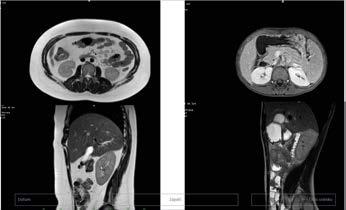

Tuk přitom neobaluje jen samotné tělo, ale také všechny vnitřní orgány, což znázorňuje obrázek magnetické rezonance níže, kdy nalevo je dívka s těžkou obezitou a napravo chlapec s normální váhou.